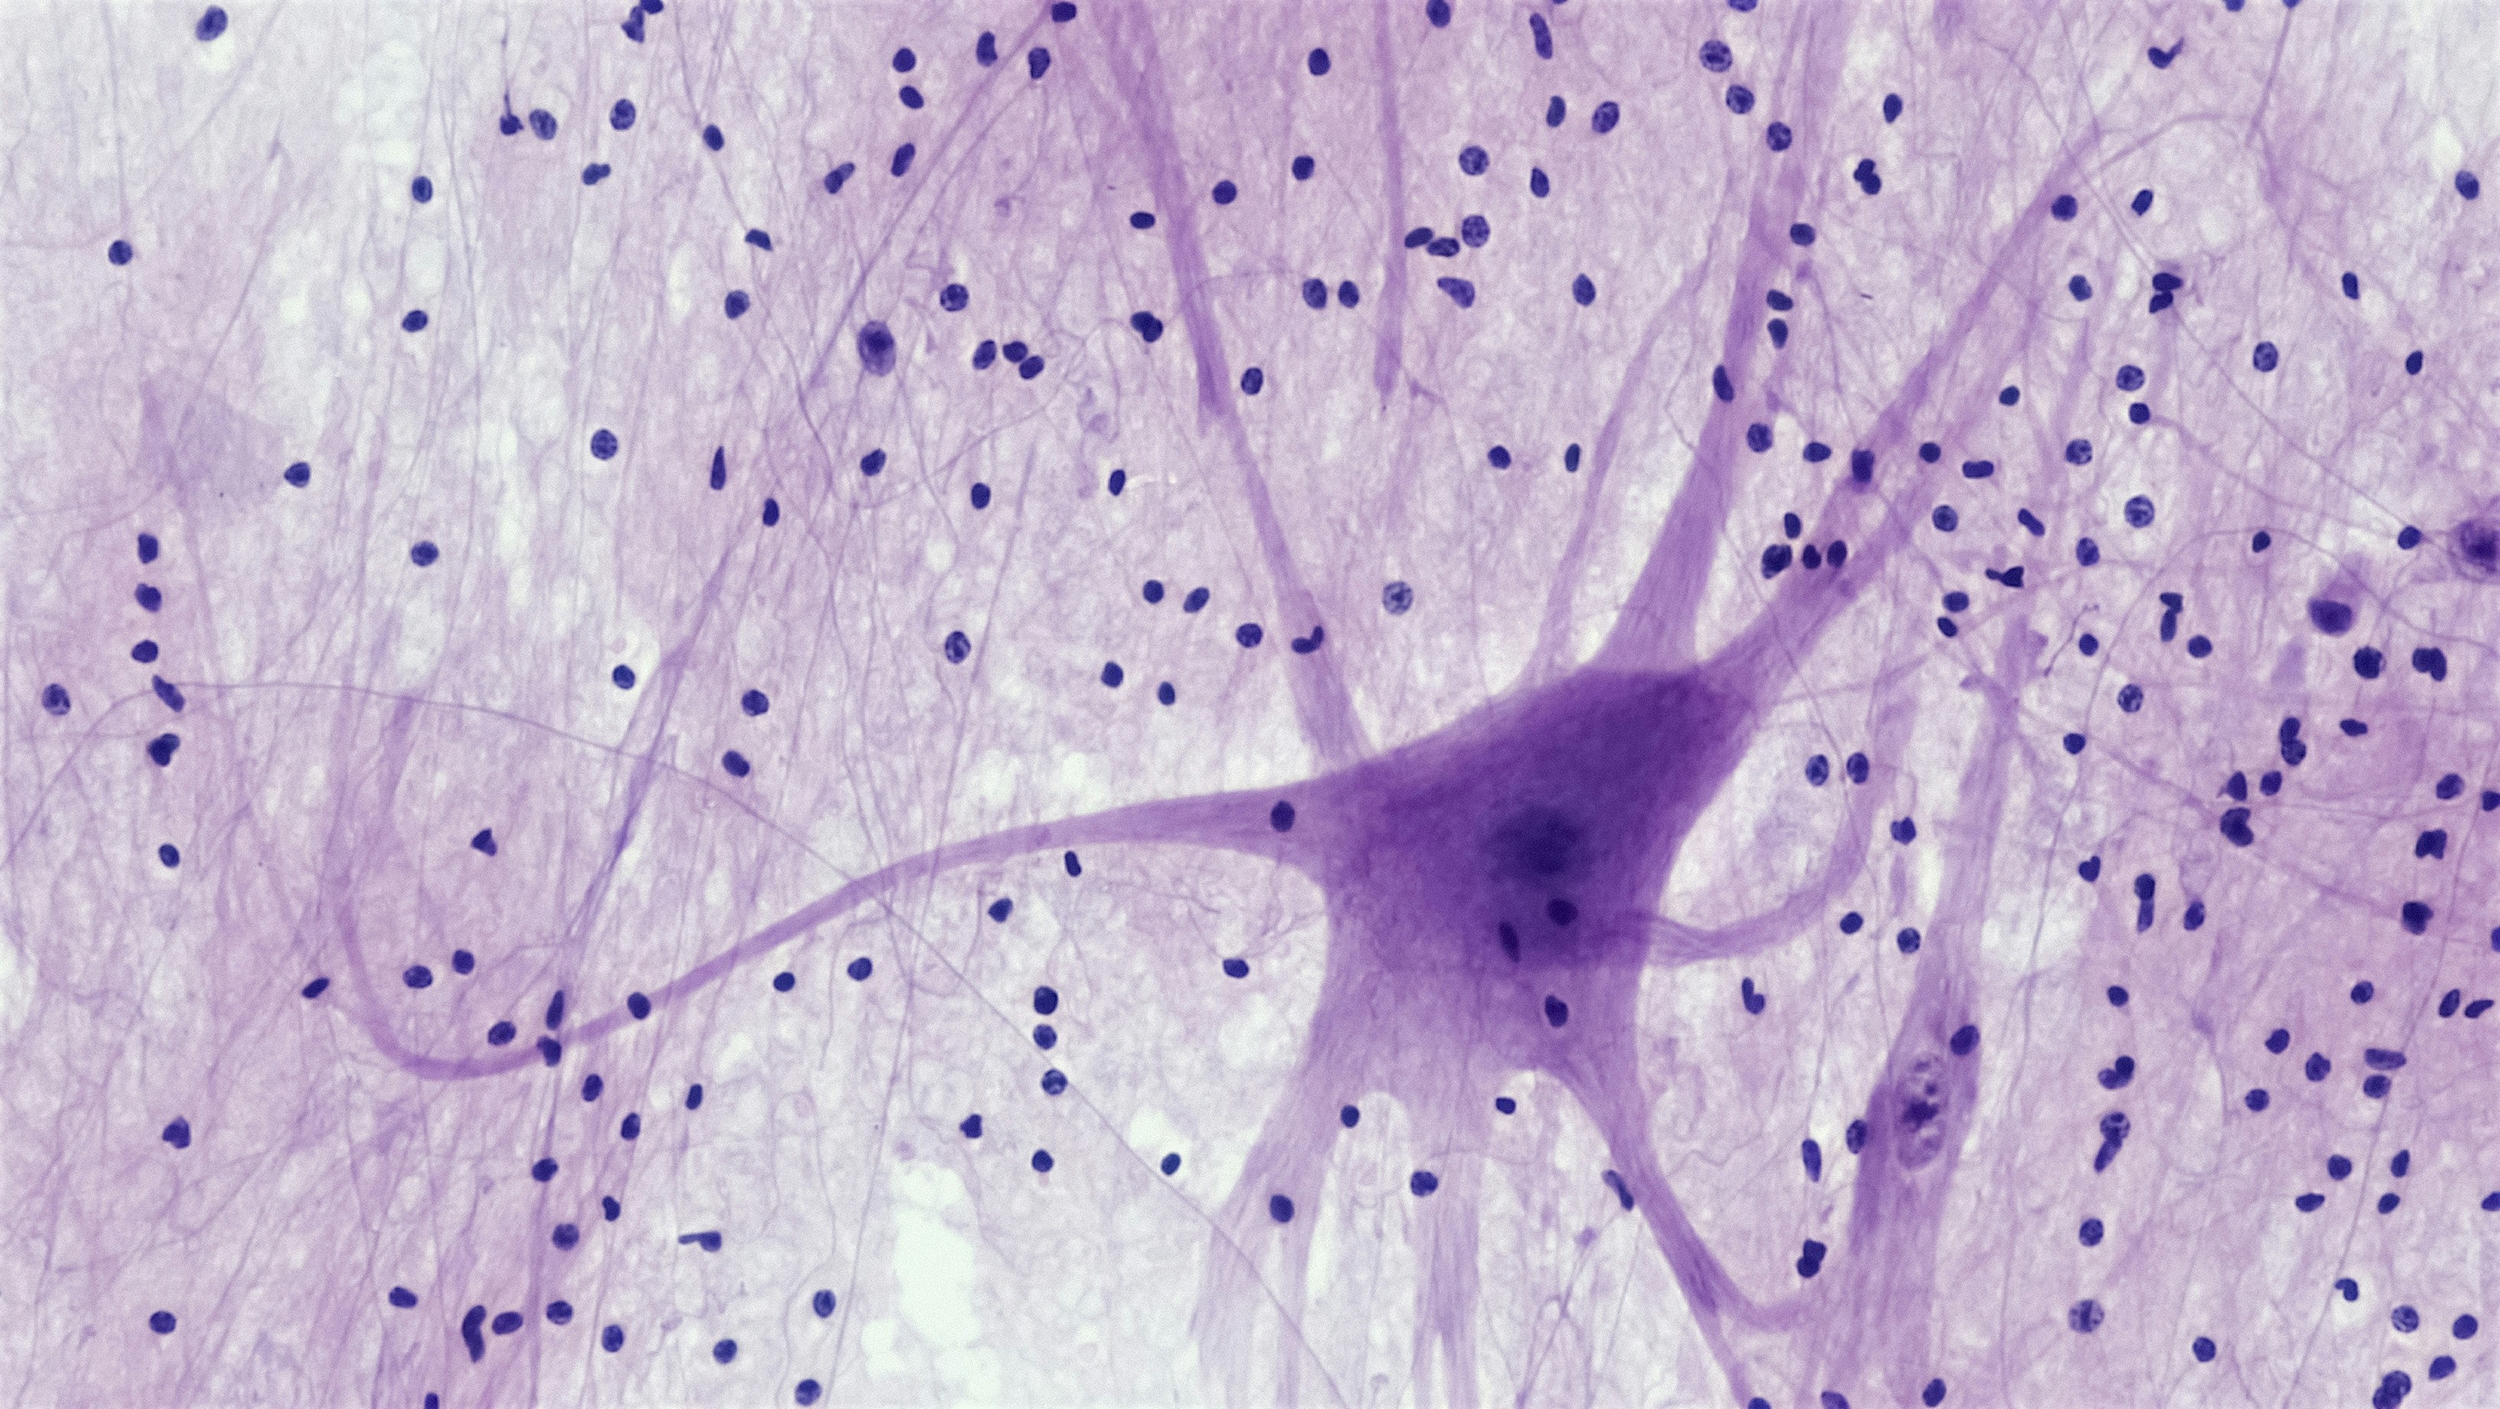

Amyotrophe Lateralsklerose (ALS) ist eine fortschreitende, unheilbare neurodegenerative Erkrankung. Für Betroffene bedeutet das, mit einem sich verändernden Körper zu leben und regelmäßig Entscheidungen zur eigenen Versorgung zu treffen. Gleichzeitig sind Ärzt:innen und Forschung auf verlässliche Verlaufsdaten angewiesen, um Therapie, Versorgung und Erkenntnisse zu verbessern.